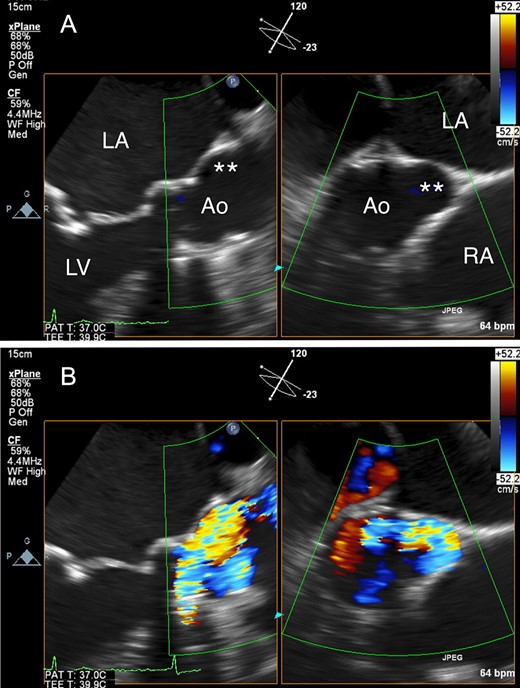

An 80-year-old woman, who had undergone aortic valve replacement with a 23-mm Björk-Shiley valve and open mitral commissurotomy at our hospital for multivalvular rheumatic heart disease at age 51, had chest tightness during exertion after many years of uneventful, asymptomatic clinical development. Follow-up transthoracic echocardiographic examinations over the past several years showed a normal left ventricular volume and ejection fraction, and moderate mitral stenosis (mitral valve area: 1.5 cm2) and an elevated peak prosthetic aortic jet velocity of 300-350 cm/s had been maintained within the boundary area without worsening. Cardiac computed tomography (CT) angiography revealed no significant obstructive coronary disease, but an unexpected saccular ascending aortic aneurysm (maximum transaortic diameter: 51 mm) arising from the posterior ascending aortic wall was observed (Fig. 1A). Transesophageal echocardiography (TEE) revealed eccentric systolic flow jets through the tilting disc valve prosthesis directly impinging on the saccular aneurysm (Fig. 2A and B, Video 1). In addition, cardiac CT angiography (systolic images) and TEE confirmed that the Björk-Shiley valve with a normal leaflet opening angle (Fig. 1C–E) was implanted with its major opening directed toward the non-coronary sinus, and was unpredictably tilted by the elevation of the prosthesis in the right-coronary sinus (Fig. 1B). The patient underwent reoperation for her ascending aortic aneurysm and possible stenosis of the prosthetic aortic valve. The ascending aorta was opened after aortic cross-clamping, and the prosthetic aortic valve and aortic aneurysm were inspected from the inside. Since the orifice of the aneurysm was located on the edge of the aortotomy suture line in the posterior wall of the ascending aorta, the lesion was probably considered a postsurgical false aneurysm. Although the Björk-Shiley valve prosthesis had no restricted leaflet motion without any obvious structural deterioration, thrombus, or abnormal pannus, it was causing an elevated transprosthetic velocity. Therefore, we decided to replace this old mechanical prosthesis with a 21-mm bovine pericardial bioprosthesis (Carpentier-Edwards Magna Ease Aortic Valve: Edwards Lifesciences, Irvine, CA, USA). The ascending aorta was replaced with a 26-mm Dacron prosthetic graft (J-Graft: Japan Lifeline Co., Ltd., Tokyo, Japan). The operative course was uneventful, and the patient recovered from surgery and has been free of complaints for almost three years.

(A) Transesophageal echocardiography (TEE) revealed a saccular ascending aortic aneurysm arising from the posterior ascending aortic wall just above the sino-tubular junction. (B) TEE with color Doppler revealed eccentric systolic flow jets through the tilting disc valve prosthesis directly impinging on the saccular aneurysm. Ao: aorta; LA: left atrium; LV: left ventricle, RA: right atrium; Double asterisk: saccular aneurysm.

In the present case, preoperative TEE revealed eccentric systolic flow jets directly impinging on the saccular ascending aortic aneurysm through the tilting disc valve prosthesis. Girdauskas et al. demonstrated histologically that the ascending aortic wall in patients with BAV stenosis was more damaged at the point on which the systolic transvalvular flow jet impinged [4]. Barker et al. conducted a cardiovascular magnetic resonance imaging study on BAV syndrome and reported that the position of flow jet impingement at the ascending aortic wall corresponded to elevated wall shear stress (WSS), i.e. a well-known stimulus leading to flow-induced vascular remodeling [5]. It is therefore reasonable to assume that direct impingement of the eccentric transvalvular flow jets on the aortotomy suture line might have contributed to the development of the saccular ascending aortic aneurysm in our patient.